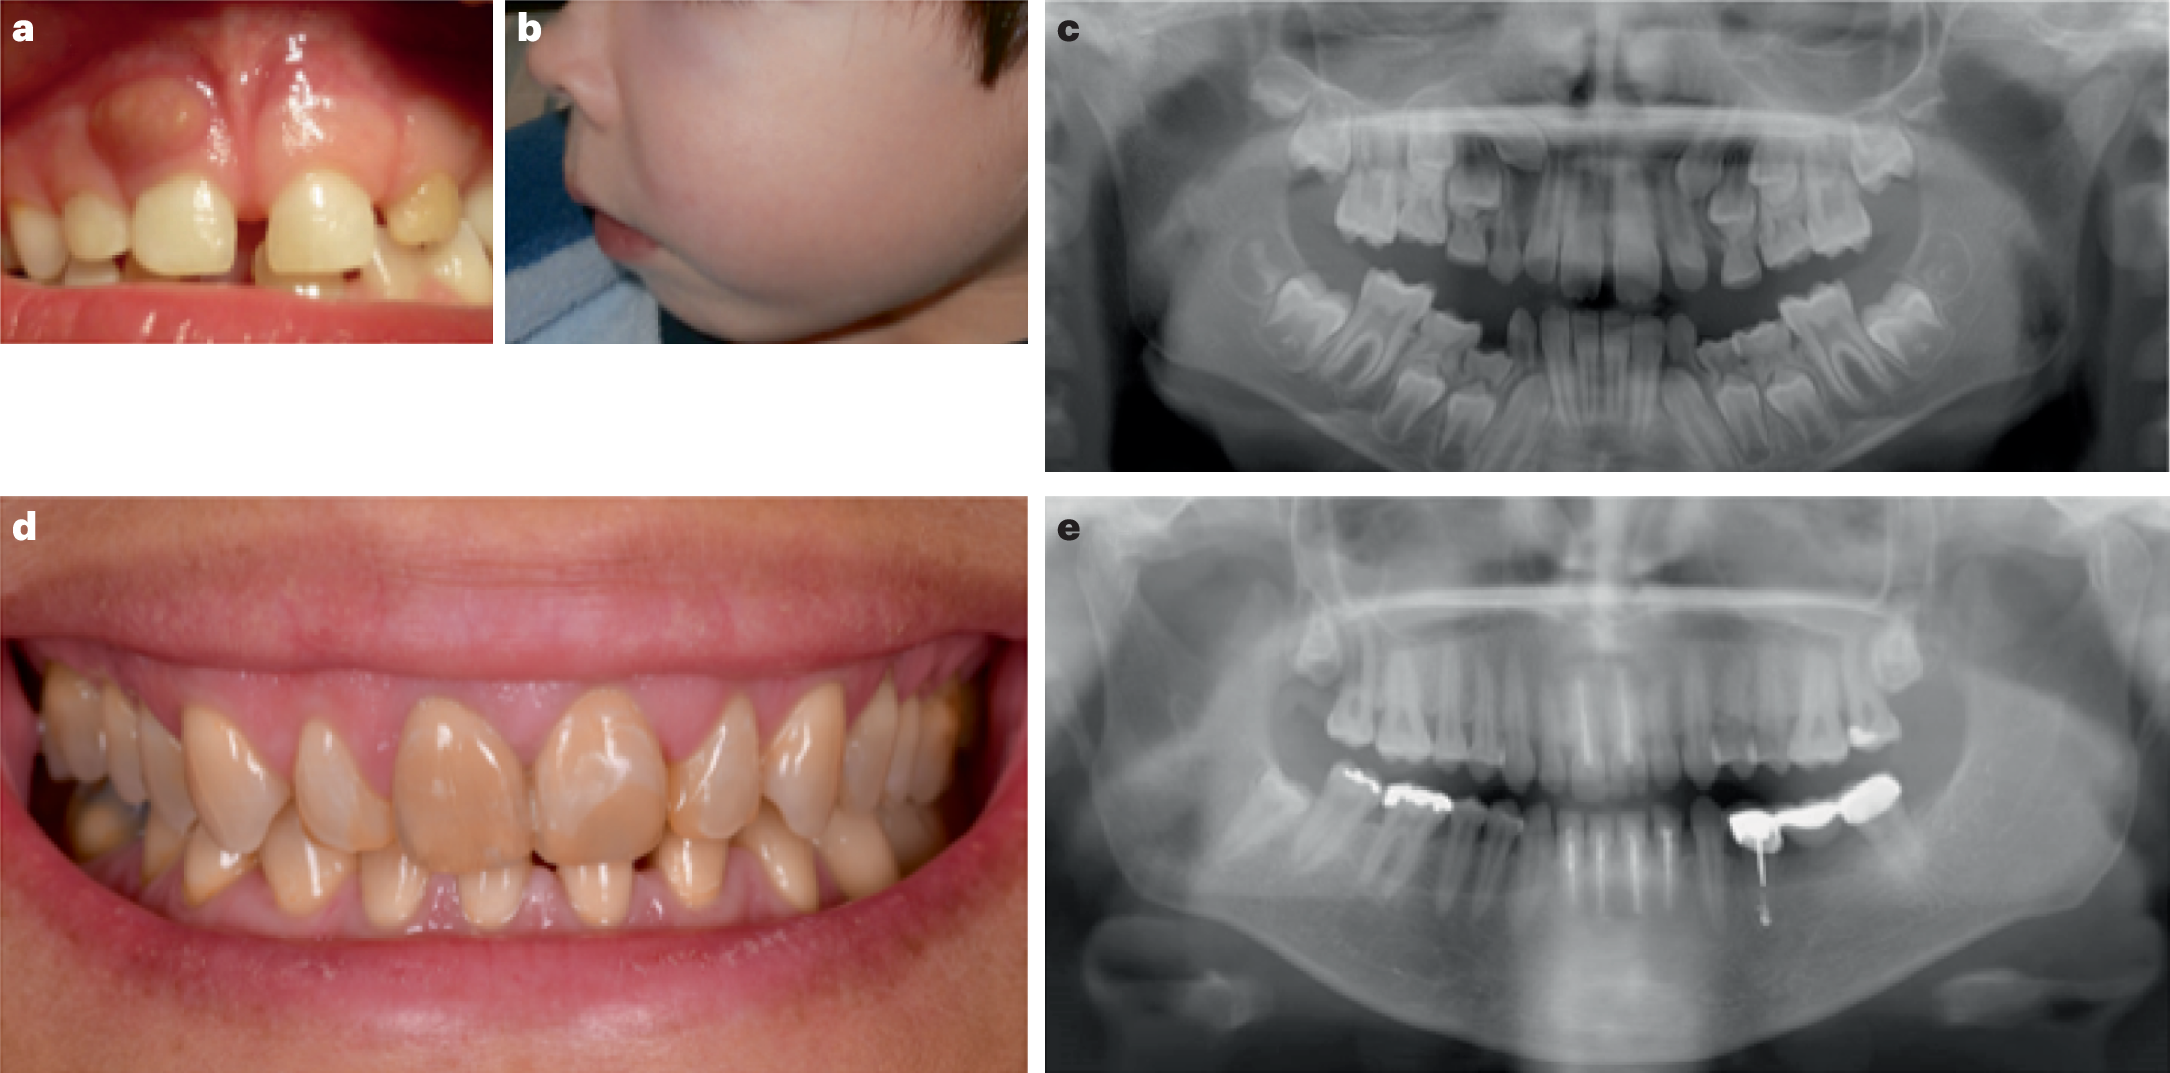

Fig. 2: Oral manifestations of X-linked hypophosphataemia.

a, Oral clinical view of a 5-year-old male patient with X-linked hypophosphataemia (XLH) showing a spontaneous dental abscess on the right upper temporary central incisor. The tooth shows no discoloration or carious lesion and the child and his mother reported no history of trauma. b, Maxillo-facial cellulitis due to spontaneous necrosis of the left upper temporary canine in the same patient at the age of 7 years. c, Panoramic radiograph of the same patient at the age of 8 years showing mixed dentition with characteristic dental features of XLH, including a normal (slightly thin) enamel layer, a radiolucent dentin layer with enlarged pulp chambers and prominent pulp horns on both temporary and permanent teeth. d, Oral clinical view of a 49-year-old woman with XLH who was diagnosed at the age of 4 years. The patient was treated with oral phosphate supplements and active vitamin D during growth for 12 years before the treatment was stopped at the age of 16 years. This treatment was resumed for 4 years from the age of 40 years before being replaced with burosumab, which had been taken for 5 years. e, Panoramic radiograph of the same patient showing generalized horizontal alveolar bone loss and teeth treated endodontically owing to dental infections.